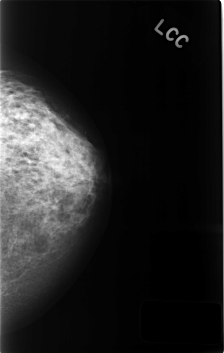

ics_version 1.0 filename C-0440-1 DATE_OF_STUDY 21 7 1995 PATIENT_AGE 48 FILM FILM_TYPE REGULAR DENSITY 3 DATE_DIGITIZED 23 11 1998 DIGITIZER LUMISYS LASER SEQUENCE LEFT_CC LINES 4584 PIXELS_PER_LINE 2912 BITS_PER_PIXEL 12 RESOLUTION 50 NON_OVERLAY LEFT_MLO LINES 4592 PIXELS_PER_LINE 2880 BITS_PER_PIXEL 12 RESOLUTION 50 OVERLAY RIGHT_CC LINES 4552 PIXELS_PER_LINE 2920 BITS_PER_PIXEL 12 RESOLUTION 50 NON_OVERLAY RIGHT_MLO LINES 4584 PIXELS_PER_LINE 2888 BITS_PER_PIXEL 12 RESOLUTION 50 NON_OVERLAY |